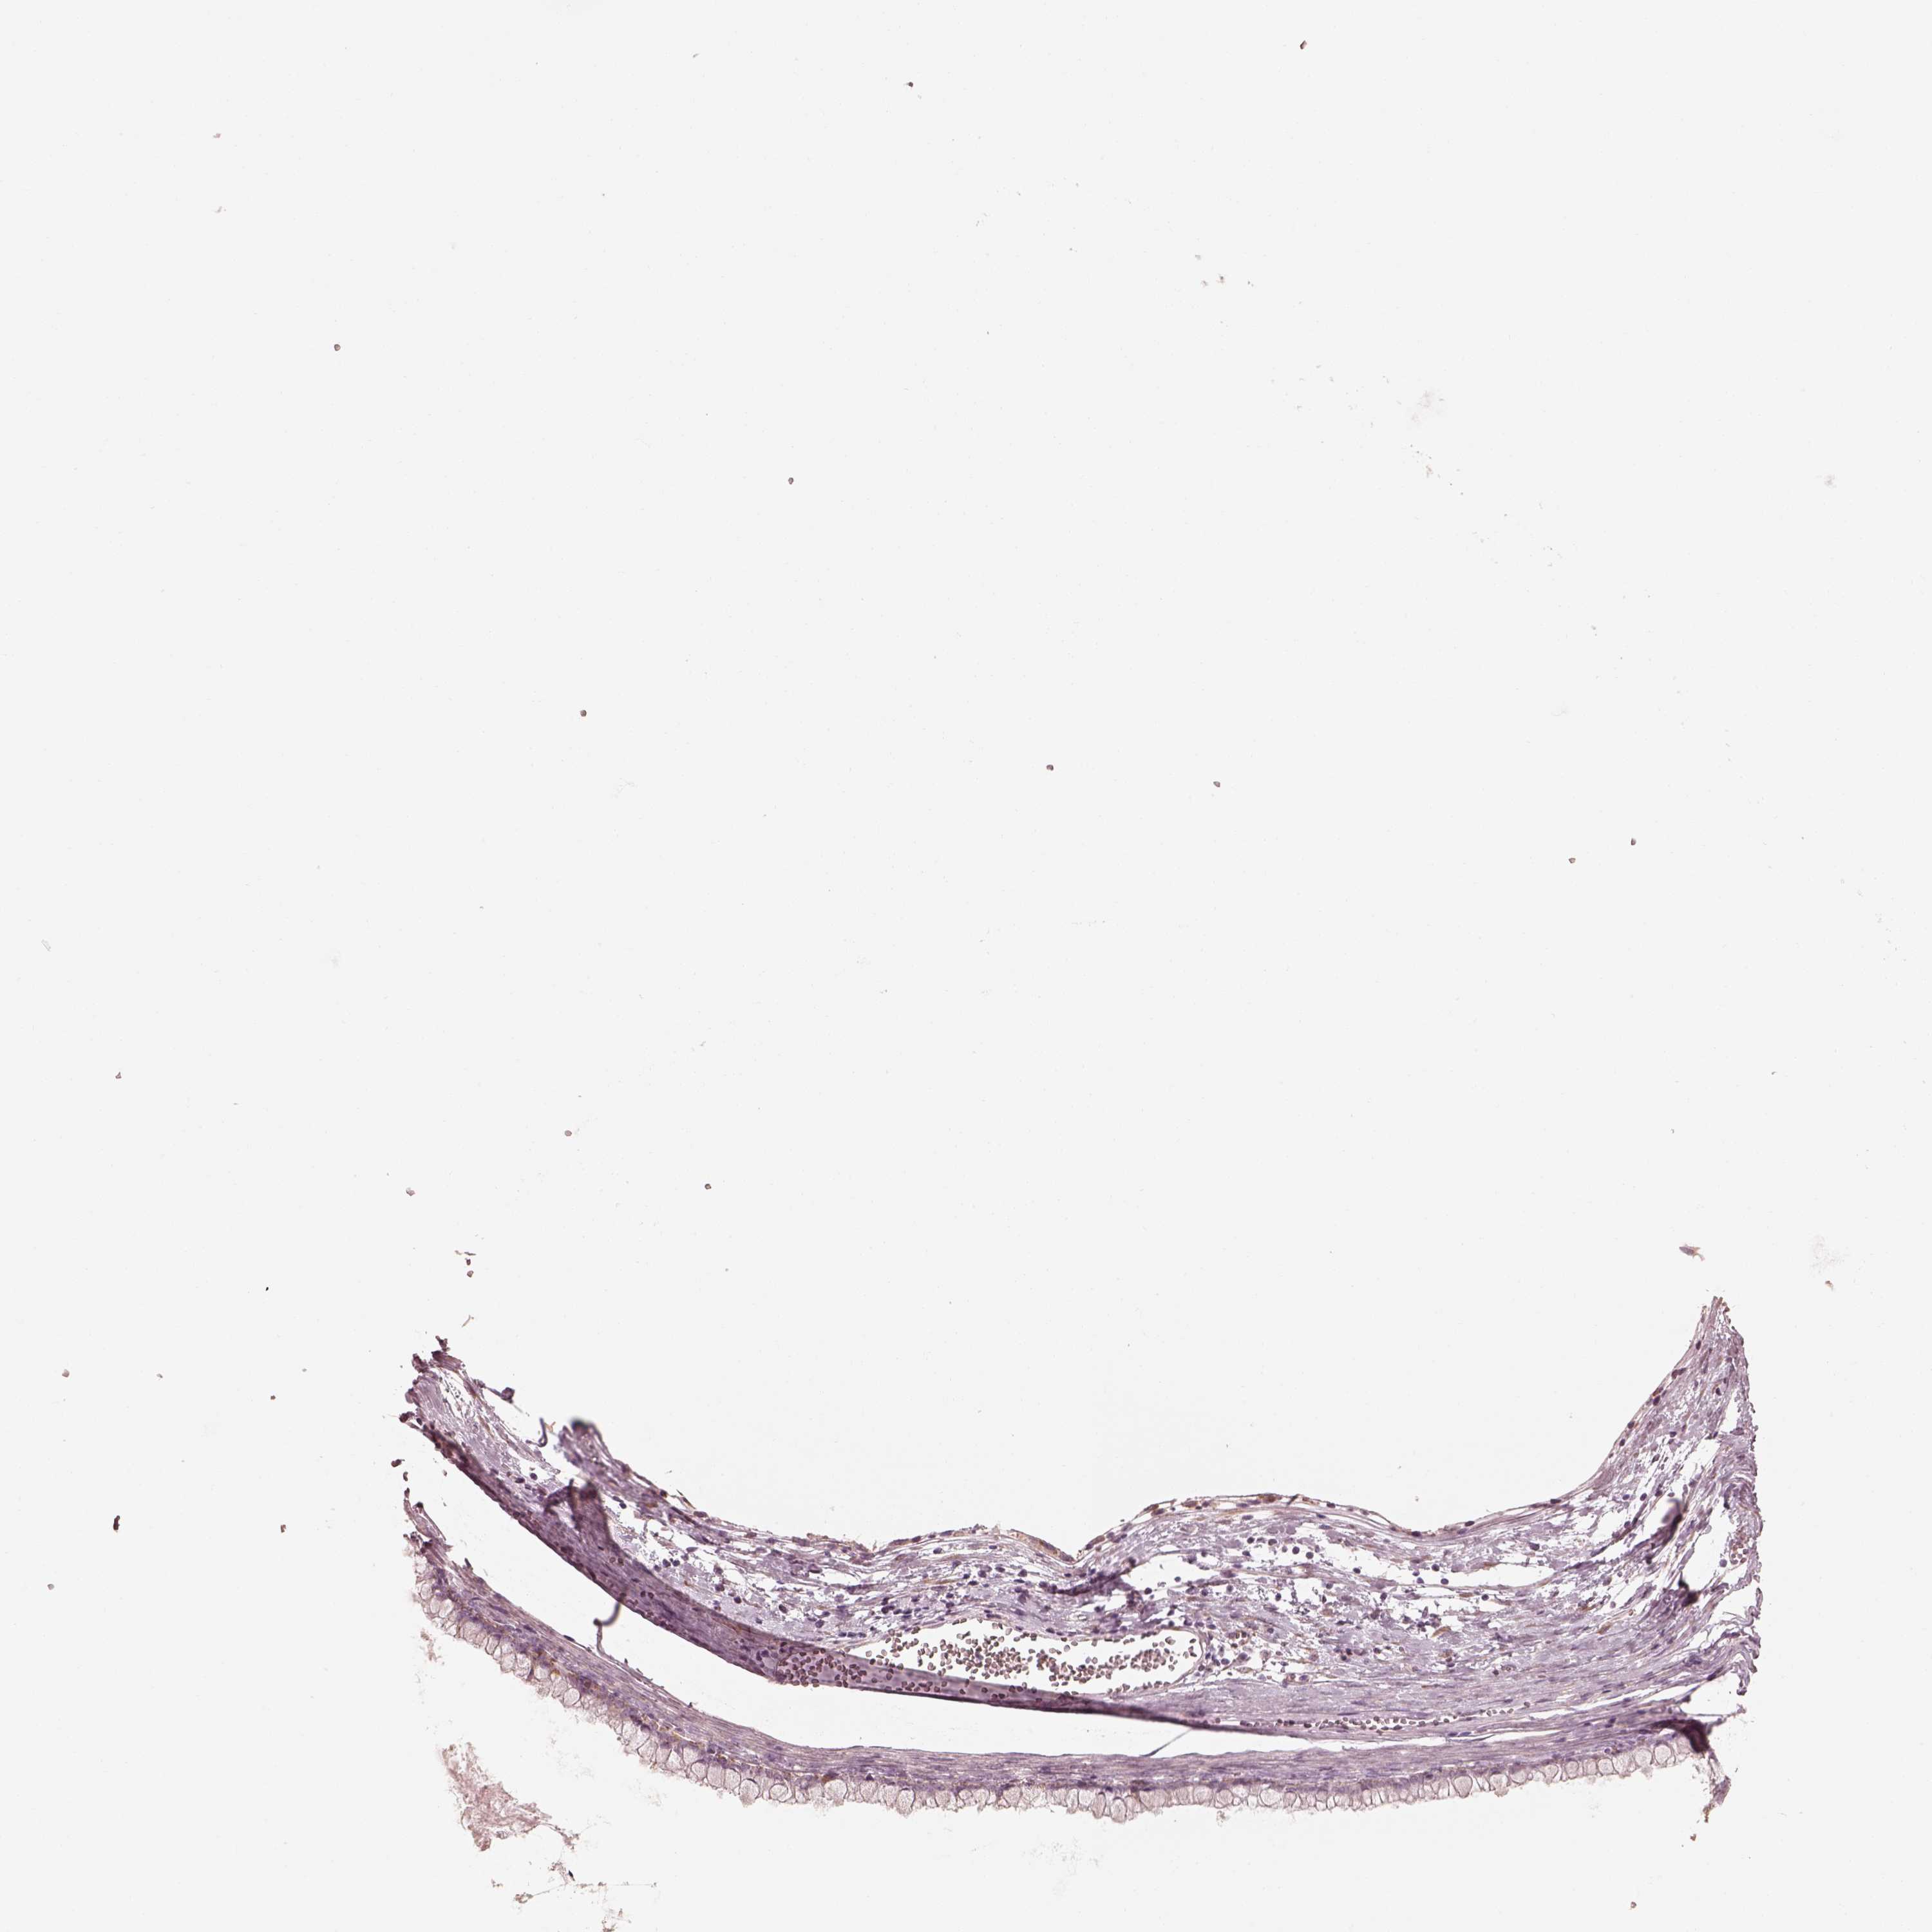

OVARIAN CANCER - Protein expressioni

A mouse-over function shows sample information and annotation data. Click on an image to view it in a full screen mode. Samples can be filtered based on level of antibody staining by selecting one or several of the following categories: high, medium, low and not detected. The assay and annotation is described here.

Note that samples used for immunohistochemistry by the Human Protein Atlas do not correspond to samples in the TCGA dataset.

Antibody stainingi

Antibody staining in the annotated cell types in the current human tissue is reported as not detected, low, medium, or high, based on conventional immunohistochemistry profiling in selected tissues. This score is based on the combination of the staining intensity and fraction of stained cells.

Each image is clickable and will lead to virtual microscopy that enables deeper exploration of all samples and also displays staining intensity scores, fraction scores and subcellular localization as well as patient and tissue information for each sample.

Antibody HPA003160

Antibody HPA048156

Cystadenocarcinoma, mucinous, NOS

Carcinoma, endometroid

Cystadenocarcinoma, serous, NOS